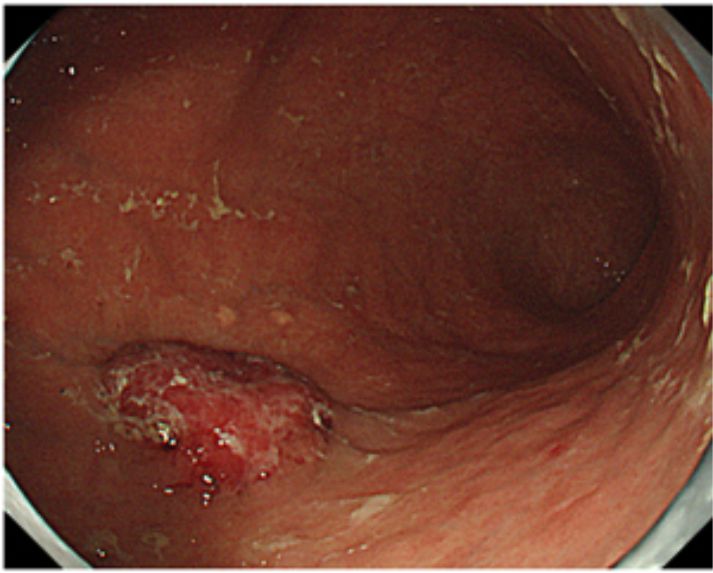

Endoscopic appearance of gastric cancer in early stage